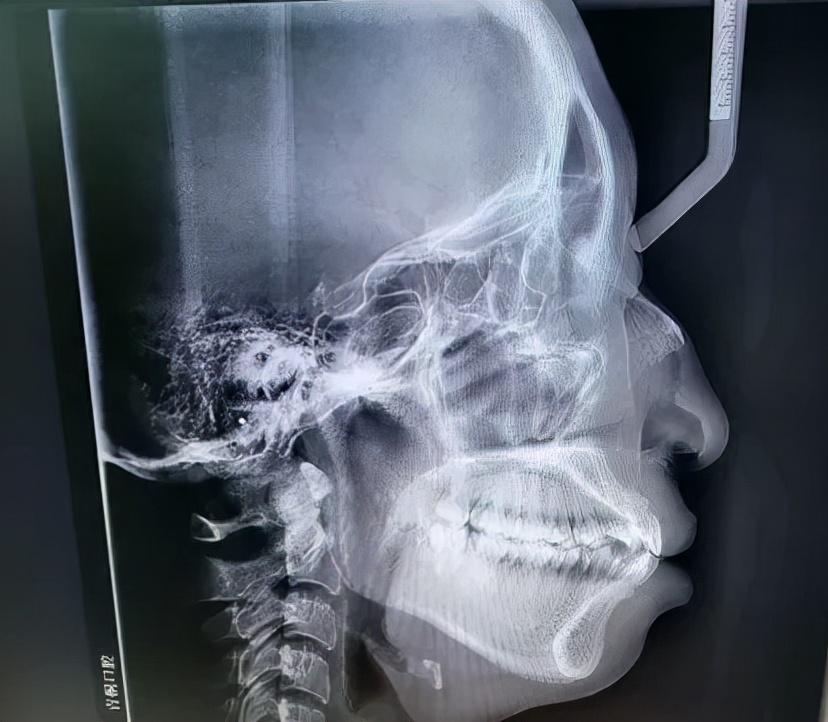

如何判斷是否屬于骨性口凸,不是光看照片或是照鏡子就能判斷的,必須要拍片檢查,通過專業(yè)的頭影測量數(shù)據(jù)才能知道。骨性外凸通常包括以下幾種具體情況。

1、上頜骨發(fā)育過度:上頜骨過度發(fā)育導(dǎo)致凸嘴。2、下頜骨發(fā)育不全:很多人認(rèn)為骨性嘴凸一定是上頜骨突出造成的,但也不一定,也有一些人的嘴看起來很凸,是因為下頜骨發(fā)育不全(即下頜骨后縮)。3、雙下巴問題:當(dāng)然還有一種情況是上下頜骨都有問題,這也是比較常見的一種情況,比如上頜骨突出,下頜骨發(fā)育不全(下頜骨后縮),看起來就像嘴巴突出和沒有下巴的結(jié)合體。